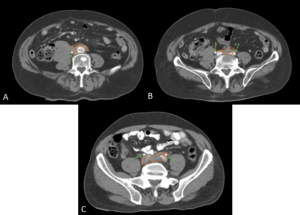

MULTIDETECTOR COMPUTED TOMOGRAPHY (MDCT)

MDCT may fail to demonstrate abnormalities in approximately one third of surgically proven RPF cases.

RPF typically appears as a well-defined, irregular paraspinal soft-tissue mass, isodense to the psoas muscle and without lateral extension beyond it. Most often centred at L4–L5 near the aortic bifurcation, it may extend cranially towards the renal hila or, less commonly, caudally to involve pelvic structures. Baseline Hounsfield units (HU) values and the diameter of the retroperitoneal tissue can assist in assessing inflammatory activity. [1,3,5-8]